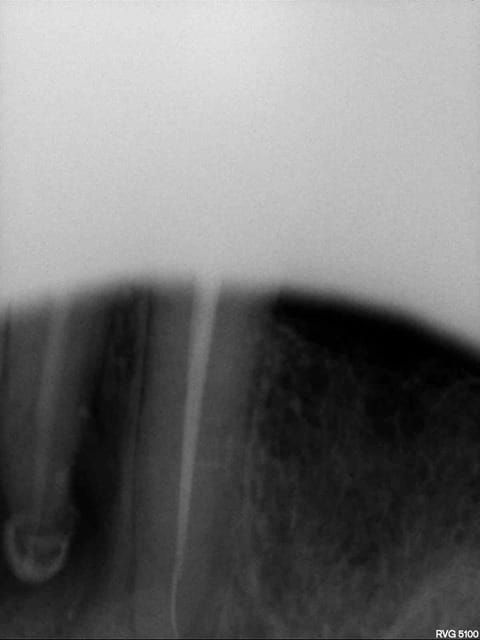

Voila mes deux perles, je me doute bien que l'infection sur la 46 a peu de chance de disparaitre, mais on remarquera sur la 13 la belle continuité de l'instrument sur le gutta qui cache bien son jeu! :-))

Salut. en fait tout dépend du type d'instrument et surtout de la zone de casse. dans les 2 cas la cassure dans le tiers apical rend la dépose compliquée voir impossible.

En général il faut essayer de faire un by pass: cad de passer un instrument manuel à côté.

Avec un peu de chance sur la molaire les 2 canaux mésiaux se rejoignent à l'apex et ça pourrait marcher. mais très compliqué quand même, d'autant plus si tu n'as pas d'aides optiques pour te donner un coup de main.

J'espere que les deux canaux se rejoignent, ce serait super, mais je me fais pas trop d'espoir, heureusement j'ai donné un mauvais pronostic au patient avant meme de commencer, je lui ai dit qu'on essaye, si ca marche pas extraction.